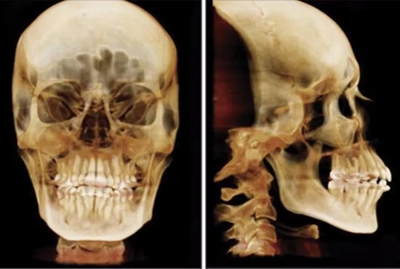

患者曾行正畸治療,現覺笑容不美觀前來就診?;颊哒嬗^及側貌示下頜發(fā)育不足,偏高角,唇閉合不全。上下頜中線齊。覆合、覆蓋4毫米。磨牙關系及尖牙關系II類。上頜擁擠度4mm,下頜擁擠度6mm。4顆第一前磨牙在第一次正畸治療時已拔除。上下牙弓呈尖圓型,牙弓狹窄。

頭影測量分析,SNA角84°,ANB角6°,高角型,詳見下表。

患者側貌改善,下唇唇肌緊張消失,上下唇可自然閉合。磨牙及尖牙關系糾正至I類,覆合覆蓋正常。上下頜弓型糾正至卵圓形,牙弓寬度增加。頭影測量分析示SNA角81.8°,ANB角3°。頭影測量重疊圖示下頜骨向后旋轉,垂直面高度略有增加。